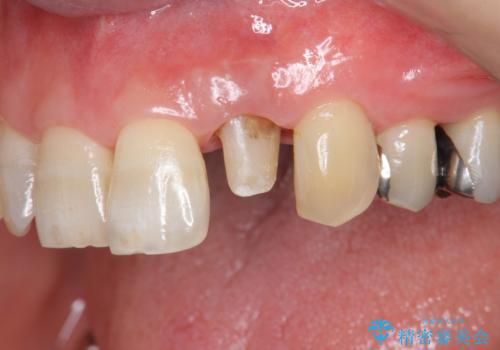

- 目立つ前歯の著しい変色の改善を求めて来院されました。

根管治療が為されたまま、クラウンの装着が行われず変色し審美障害を来している状態です。

維持を保つためのファイバーコア築盛を行い、精密なジルコニアクラウン製作を行います。